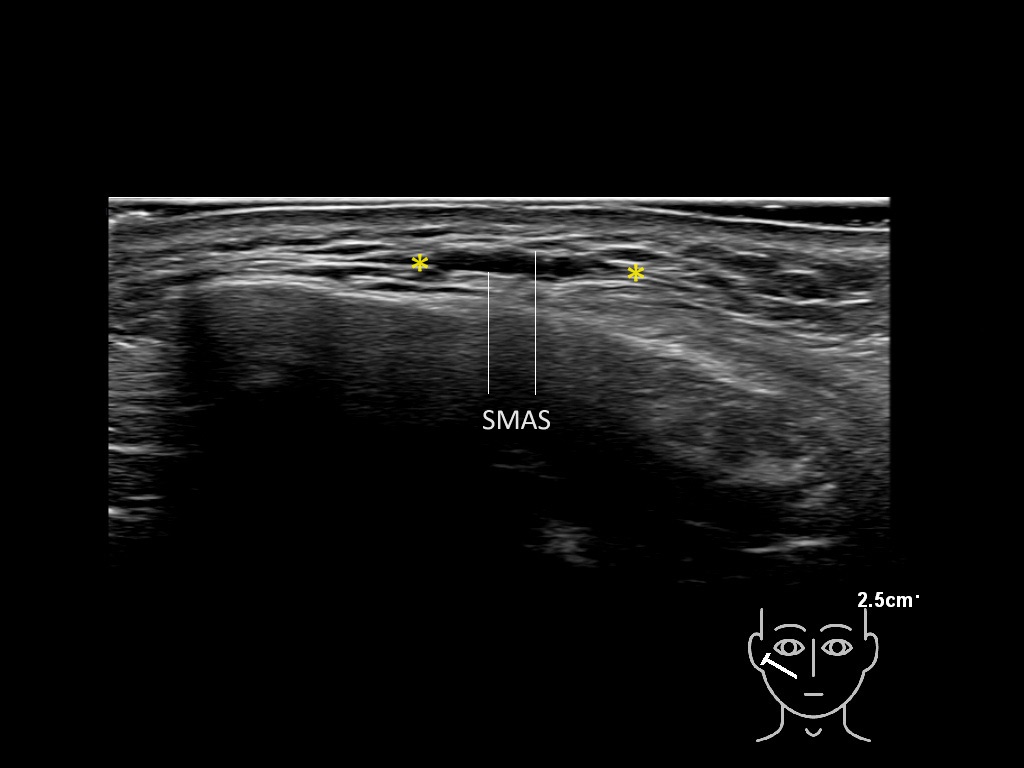

Filler deposits may end up unintentionally in the SMAS or fascial layers of the skin. Very often this will not lead to adverse events, however, adverse events ( nodules, migration / redistribution impaired muscle movement and smiling and malar edema) are are often related to filler ending up in the SMAS or fascia.

Study the first image to recognize the different layers. If you are sure about the layers, swipe to the second image to view the answer (if applicable).